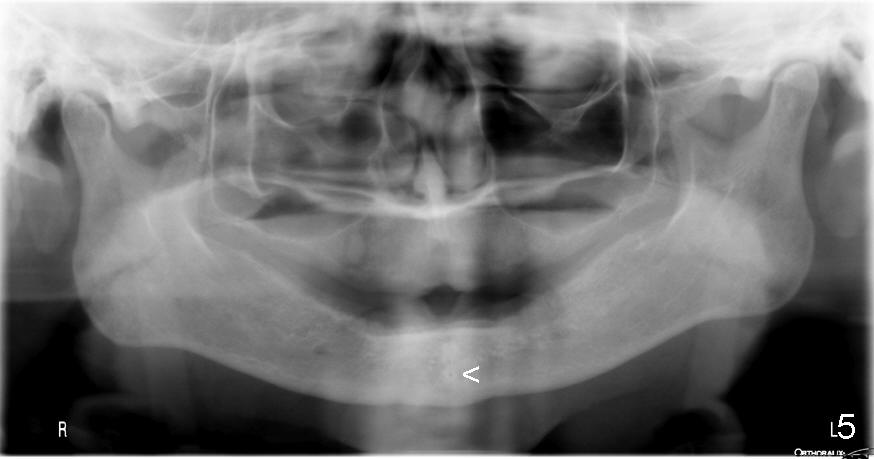

舌动脉(Lingual artery)是颈外动脉(External carotid artery)第二个前分支(图一),舌动脉末分支是舌下动脉(Sublingual artery)。舌动脉行于下颌骨舌侧(图二),它末分支舌下动脉中止于下颌骨切牙舌侧(图三),舌下动脉与颏下动脉(Submental artery,面动脉(Facial artery)分支)有吻合(箭头)。下颌骨舌侧有多个小孔(图四):正中(a, d),侧(c, e)舌孔,主要动脉穿入(1)。全景片(图五),前牙根尖片(图六)可显示舌孔(箭头, Lingual foramen)。舌孔延伸下颌骨舌侧一半(图七),下前牙植牙造成严重出血(图十,十一,2),往往是因为舌侧骨板穿孔,研究表明牙槽骨萎缩是血管意外(舌侧骨板容易破裂)主要因素(3,图八a,图九),预防方法:术前下颌骨舌侧触诊,对危险性大的病例做CT检查;术中钻洞时做下颌骨舌侧触诊,对危险性大的病例,翻瓣,暴露舌侧骨板,保护舌侧结构,使用短种植体。